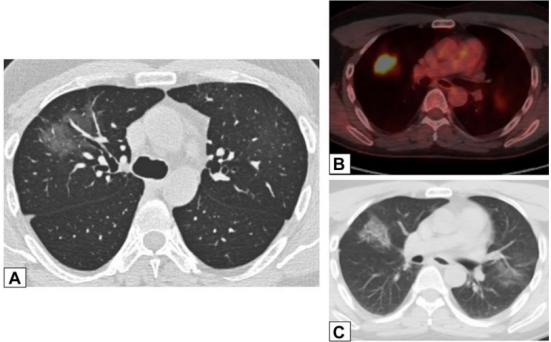

在活检证实的OP患者中,中肺(图2A)和下肺(图2B)的增强CT扫描图像显示双侧多灶性支气管血管周围实变灶。

图2 支气管血管周围实变

图源:Chest, 2022, 162(1):156-178.图3A为71岁男性,2011年7月因劳力性呼吸困难就诊,胸片显示右肺上叶实变。图3B为2012年6月再次检查显示右肺上叶异常已消失,左肺出现广泛实变。图3C为2013年6月,左肺病变消失,但右肺下叶出现新的实变。这些发现是典型的OP游走性表现。图源:Chest, 2022, 162(1):156-178.图3所示患者胸部CT可见磨玻璃影伴小叶间隔增厚和铺路石征的游走灶(图4)。由此可见,OP的实变可以发生在肺的任何部位,边界清晰或模糊,呈游走性特点。图源:Chest, 2022, 162(1):156-178.OP的实变可以呈局灶性、多发性和弥漫性,也可以表现为结节或肿块。图5所示患者为70岁女性,COVID-19确诊9个月后出现持续气促,CT平扫图像显示支气管血管周围多灶性肿块样实变。在类固醇治疗后症状显著改善,实变消退,推测诊断为OP。图源:Chest, 2022, 162(1):156-178.实变常伴支气管充气征,可伴散在的磨玻璃样低密度或小实质结节。以主要的或完全的磨玻璃低密度为表现者较少见。图6A所示为一名有甲状腺乳头状癌病史的47岁男性患者碘131治疗4个月后的CT平扫图像,可见右肺上叶支气管血管周围磨玻璃影。PET/CT扫描显示磨玻璃影代谢增高(图6B)。CT平扫图像显示左肺上叶新出现的磨玻璃影(图6C)。支气管活检结果与OP相符。图源:Chest, 2022, 162(1):156-178.图7为一名71岁男性患者因使用胺碘酮导致SOP的CT平扫图像,可见左肺广泛磨玻璃影,小叶间隔增厚(铺路石征)。磨玻璃低密度影合并小叶间隔增厚可表现为铺路征。